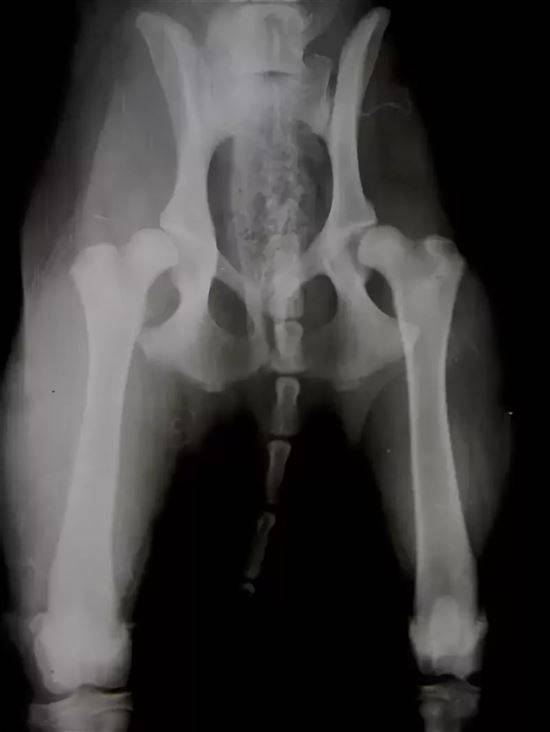

Клинический случай: собака породы лабрадор, 8 месяцев. При поступлении в клинику собака не передвигалась самостоятельно. Проведена тройная остеотомия таза на двух конечностях одновременно. Время проведения операции 1 час 40 мин.

Рис. 6-7. Результат: восстановление дорсального края вертлужной впадины через 3.5 месяца на правой конечности и полное восстановление левого тазобедренного сустава. Полное восстановление движений у собаки через 3.5 месяца после операции.